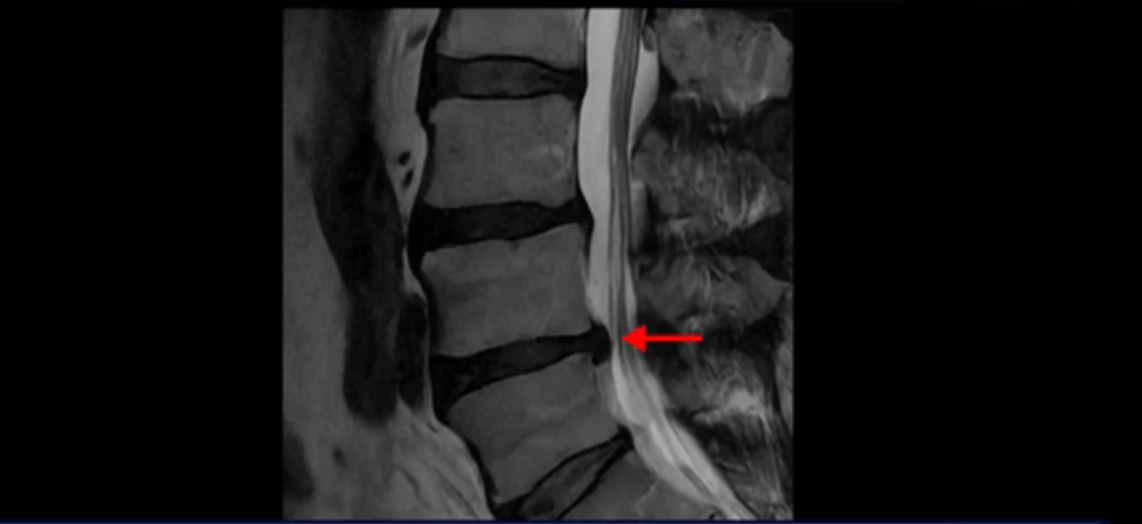

이분 MRI를 잠깐 보실까요? 보시면 두 마디가 특히 안 좋은데 3번 4번 디스크가 터져서 흘러 내려 있습니다.

보시다시피 흘러 내려온 디스크 수핵이 신경 공간의 왼쪽으로 보입니다.

그런데 이분은 4번 5번에도 디스크 파열이 있습니다.